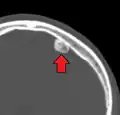

Osteoma of the frontal sinus seen on x-ray -